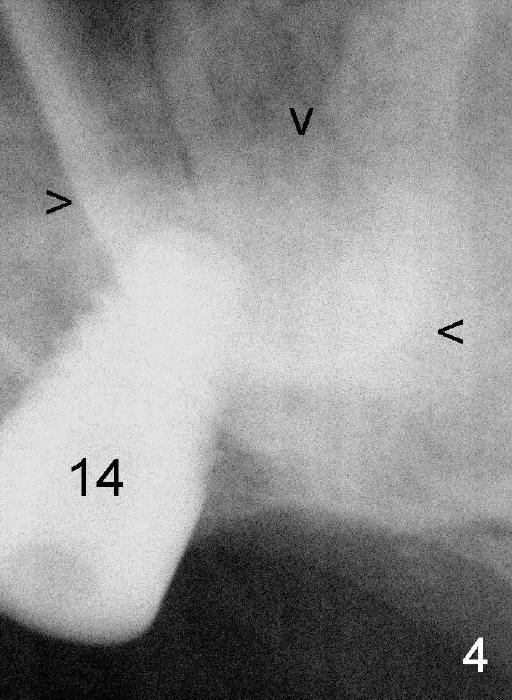

A synthetic bone graft (Osteogen) is placed in the sinus before placement of 6x11 mm implant (Fig.4: 14). X-ray appears to show light shadow around the implant (arrowheads, bone graft material). The radiopaque density increases as the graft matures, according to Manufacturer's claim.

More of the synthetic bone mixed with autogenous bone is added superficial to the apex of the implant inside the sinus.